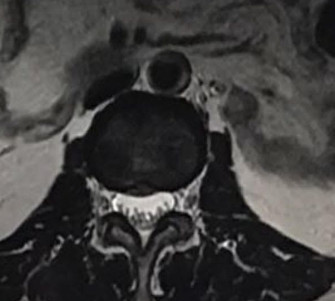

醫生會透過了解病史、檢查肌肉及神經反射狀況來尋找致病原因,也會讓病人做些引起疼痛的動作供醫生作判斷,若有需要也會要求患者做磁力共振掃描(MRI),以檢查椎間盤突出有否牽涉周邊脊椎神經線受壓。亦可從磁力共振掃描看見椎間盤失去水份及膠原蛋白而變黑,這就是退化性椎間盤的變化。

從磁力共振掃描看見椎間盤會因為失去水份及膠原蛋白而變黑,這就是退化性椎間盤的變化。